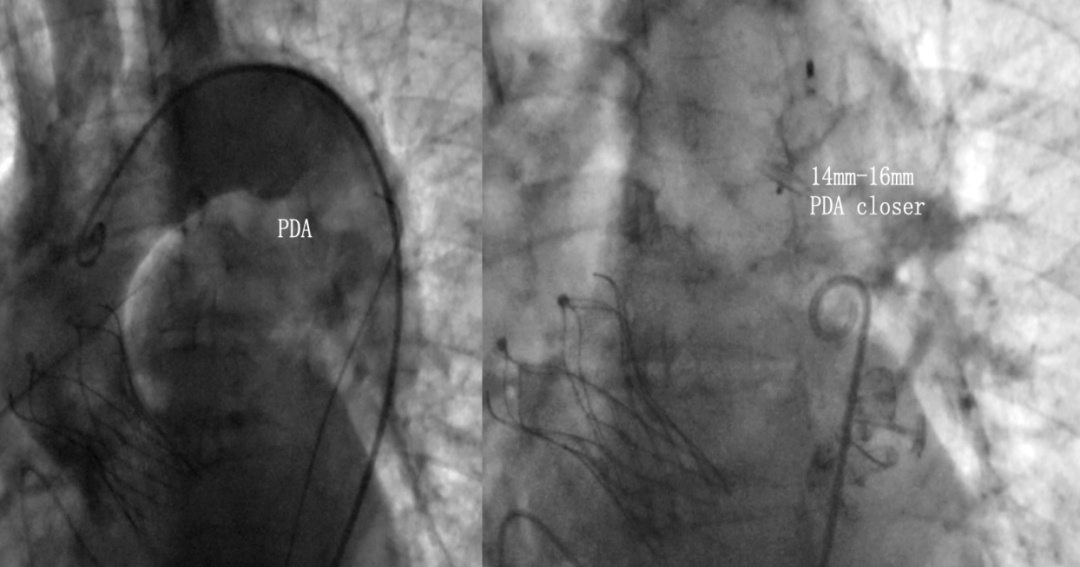

经主动脉路径植入14mm-16mm PDA封堵器

图片

术后经导管同步测压,跨瓣压差由70mmHg,改善至术后0mmHg。经食道超声显示VitaFlow®瓣膜位置固定,无瓣周漏,瓣膜形态良好。再次通过IVUS评估左侧冠脉开口面积恢复至12.76mm2,患者生命体征平稳并监护。